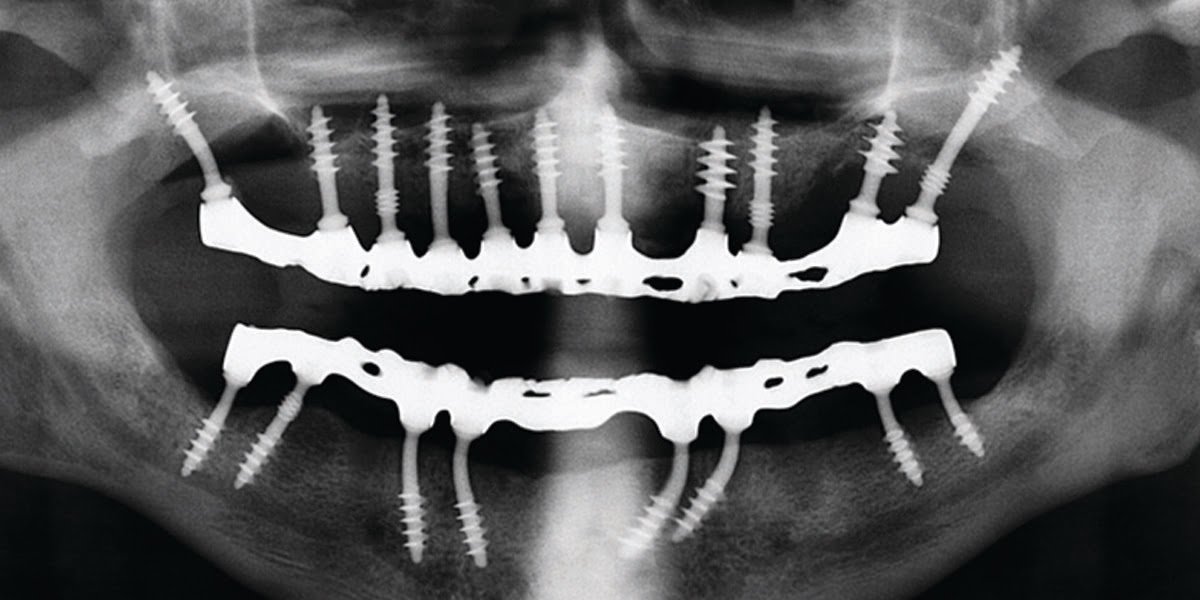

Basal implantology, also known as bicortical implants, or cortical implantology is an advanced implantology system. In basal implants, the dental implants are designed in a specific way so that they perfectly fit in the basal cortical bone areas. The basal bone offers excellent retention quality for implant retention. Basal implantology falls under the category of…